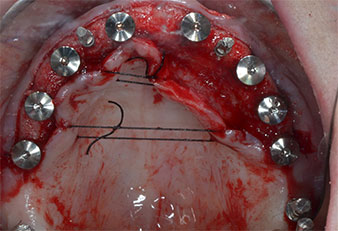

Three years later it was time for a maxillary denture of the same type. Based on CBCT planning sinus augmentation was avoided with the aid of short implants, and a surgical template was used to transfer the planned positions to the alveolar ridge (Figs. 1 and 2).

Due to the relatively hard bone (D2) in this area, the 10 mm long implant sites at positions 11 and 21 were finalized with a 4 mm diameter rotary drill, in combination with a W&H WS-75 L surgical contra-angle handpiece, the W&H Implantmed implant motor and the optional W&H Osstell ISQ module. In contrast, due to the soft bone the posterior sites were prepared to a final 3 mm diameter using the Piezomed I3P instrument. The implants were finally placed transgingivally to osseointegrate for three months (Figs. 6-10). The existing denture was retained on four provisional implants (Fig. 8).